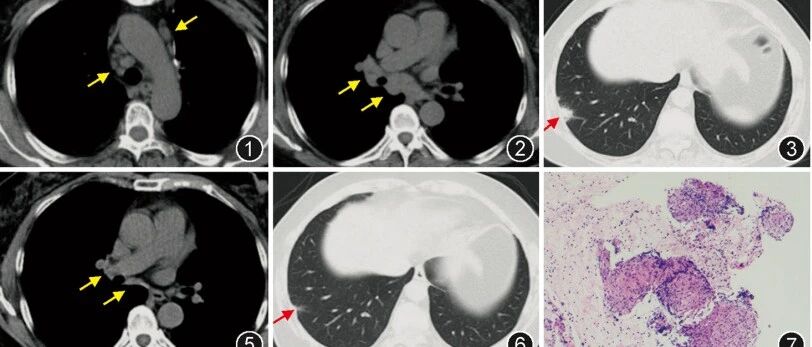

NEJM麻省总医院病例:双肺十余个空洞性结节及肿块,咳嗽发热、右眼一夜失明……致命感染因何迅速经血行...